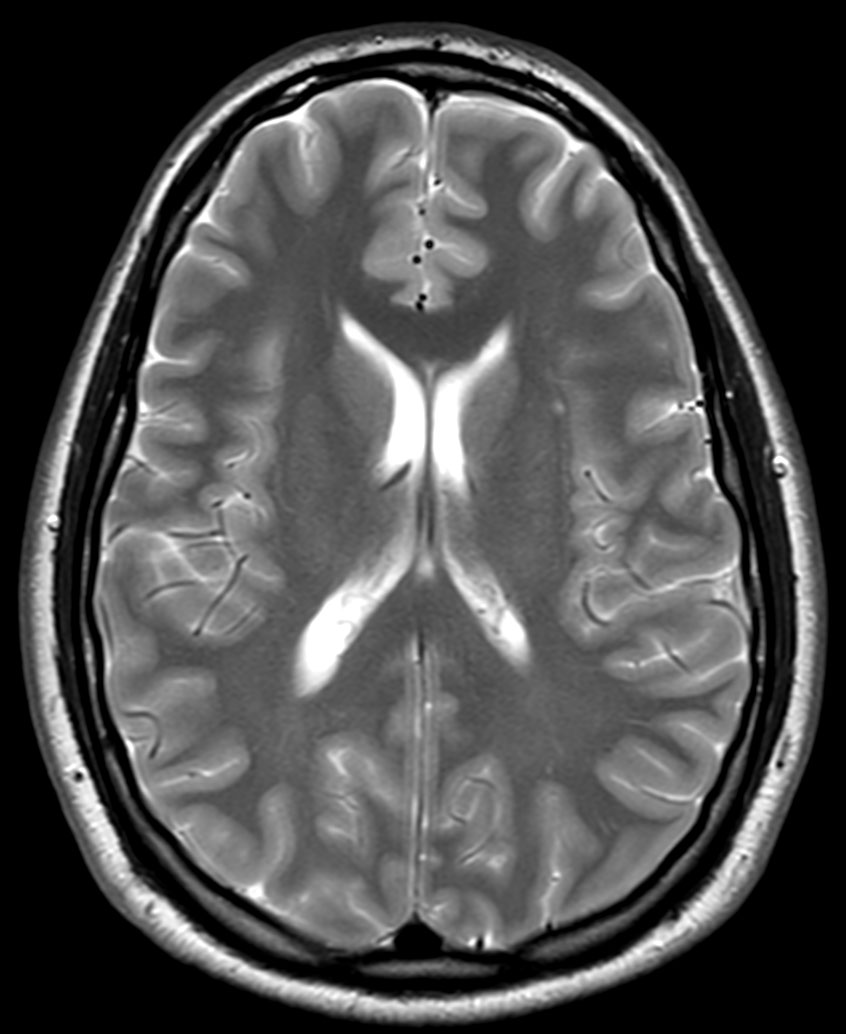

Brain imaging using ComforTone